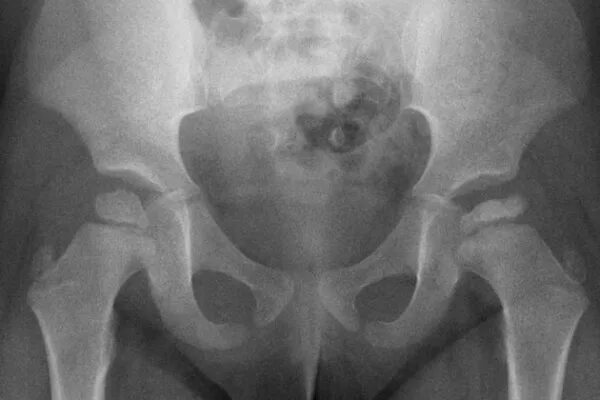

Асептический некроз инвалидность